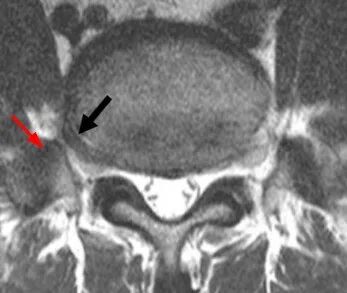

L5椎间盘呈远外侧型突出(黑箭)并与粗大的L5横突协同压迫L5神经根

注意:腰椎MR平扫常导致本病漏诊,一旦发现腰椎骶化或骶椎腰化,而患者又比较年轻,应加扫冠状位压脂序列,或是配合 CT薄层扫描进行联合诊断。